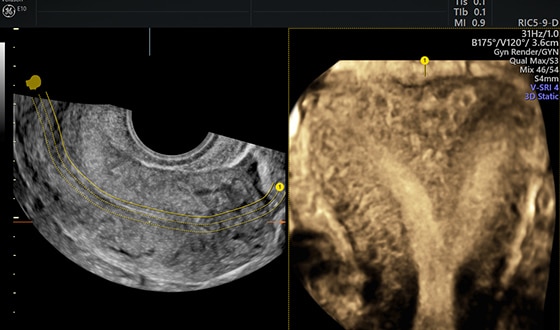

Дополнительные возможности объемной контрастной визуализации

Технология для дополнительного контрастного разрешения. Позволяет задавать дополнительную толщину среза в 3D или 4D и использовать дополнительные пресеты для костей и тканей. Может применяться в режиме реального сканирования (VCI-A), при оптимизации статических 3D-данных или OmniView-реконструкции.

Технология Advanced VCI с OmniView расширяет диагностические возможности режимов 3D и 4D, исследуя объект по любой произвольно проведенной линии и с регулируемой толщиной среза.